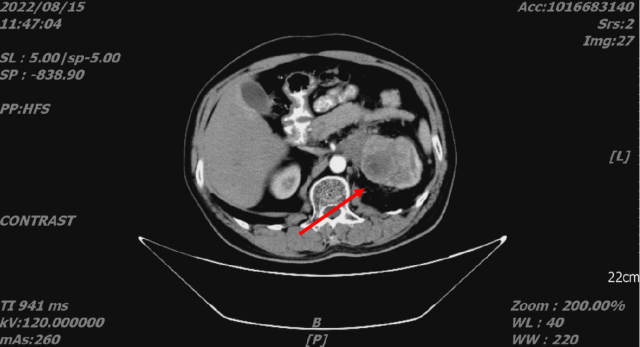

2022-08-15 CT

舒尼替尼治疗后,2022-11-11 复查 CT

1. 结合临床,左肾癌治疗后,较前片 2022-08-15 略饱满;左侧肾上腺受累;考虑肝转移,较前进展。

2. 双肺转移,较前变化不著

3. L5 双侧椎弓崩解;L2 椎体致密灶,变化不著。